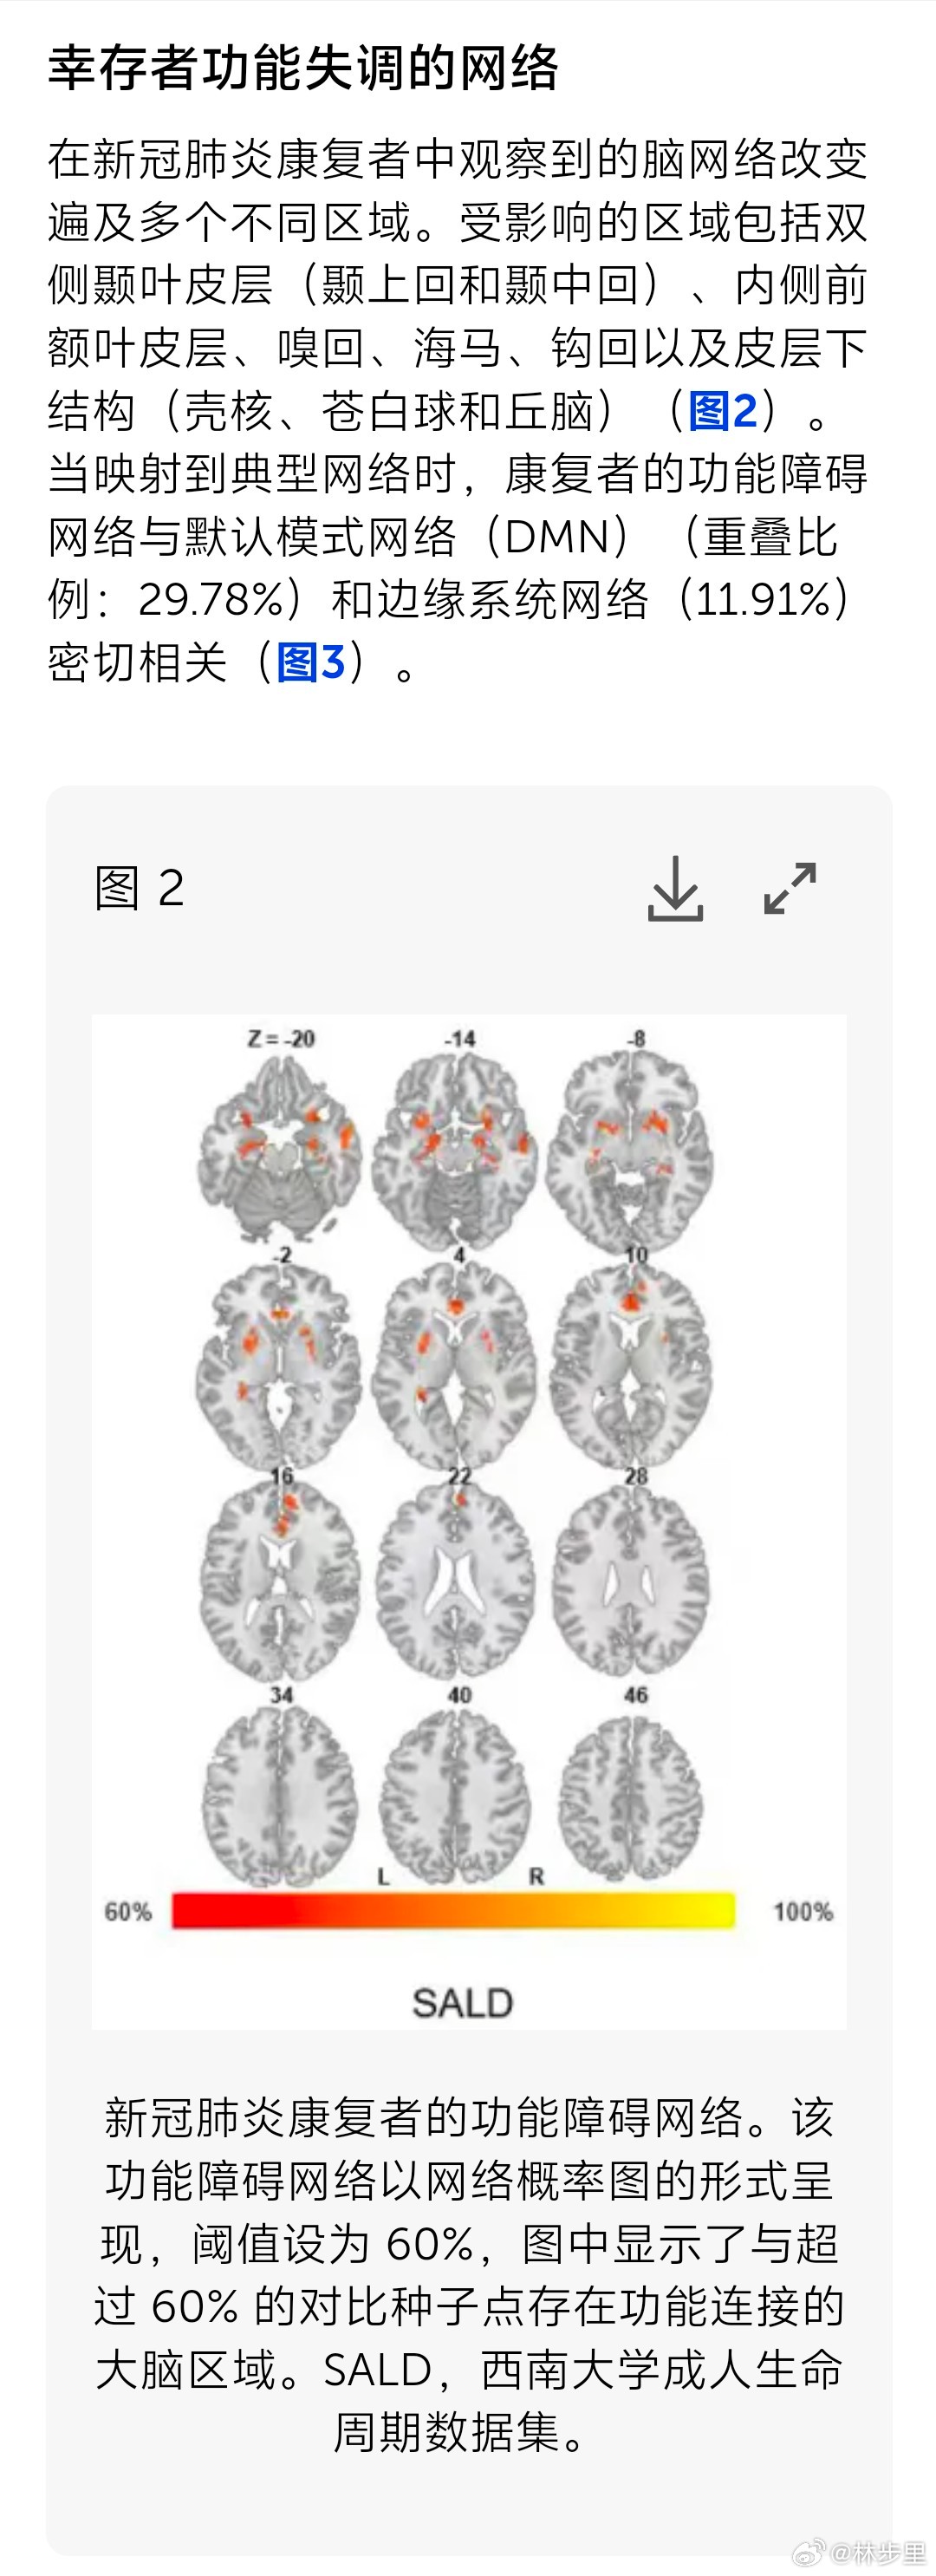

新冠伤大脑的脑网络定位。国内一项研究发现,新冠损伤的大脑网络,主要涉及默认模式系